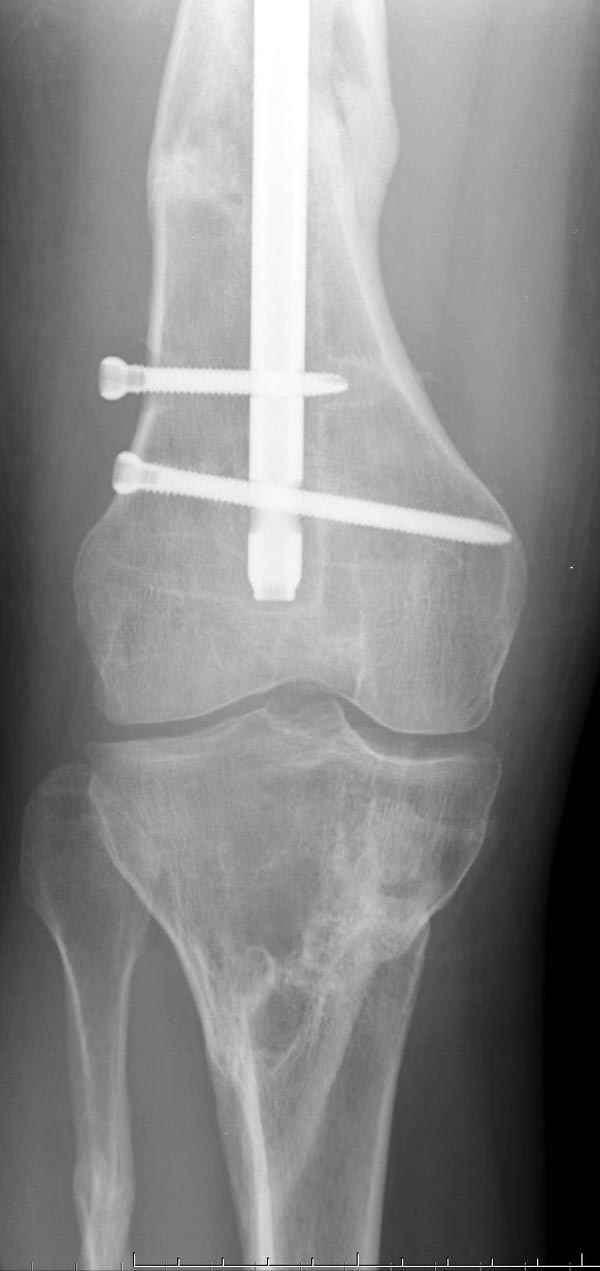

Инфекция канала и стрессовый перелом:

Представляю снимки больного с политравмой: леченного в другом мед.учреждении по поводу открытого перелома бедра, сперва аппаратом наружной фиксации, затем пластиной. Обратился к нам через 8 месяцев после удаления пластины с проблемой несросщего перелома бедренной кости, без клинических проявлении к инфицированию (не все снимки сохранены)

Рутинный интрамедуллярный остеосинтез с расверливанием и с фиксацией реконструктивным трокантерик штифтом (рис №1, №2),

если первые 4 месяца послеоперационного периода проходил без проблем, но на 5 месяце появились боли в дистальном отделе бедра и температура, т.е. симптомы медуллярного инфицирования (рис №3, №4).

Замена реконструктивного штифта “Custom made Nail” с антибиотиком (рис №5, №6),

после промывки канала с рассверливанием внутреннего кортекса, через 4 недели антибиотический штифт удалили, оспалителный процесс остановлен и бедро сросся.

Мы не дождались “Happy End”, у больного IQ в пределах 70%, через 6 месяцев вернулся после небольшой травмы, споткнувшись получил перелом

того же бедра (рис №7).

На следующий день произвели интрамедуллярный остеосинтез: этапы во время операции (рис №8, №9)

и последующих снимках (рис №10, 11, 12, 13) перелом сростается и передвигается с полной нагрузкой.

При обзоре причин перелома, на снимке №2 обнаружили, что один из стержней аппарата наружной фиксации проходил только через передний кортекальный слой, что создало стрессовую зону на бедре и в результате перелом из-за незначительной травмы.

DK> При обзоре причин перелома, на снимке №2 обнаружили, что один из

DK> стержней аппарата наружной фиксации проходил только через передний

На представленных R-граммах нет снимков с АВФ. На снимке №4 дистальный статический винт не доходит до второго кортикала. Если это имелось ввиду, то хотелось бы уточнить, могло ли это привести к повторному перелому бедра, в котором интрамедуллярный штифт отсутствовал.

На снимке N2 виден канал от стержня во фронтальной плоскости, на уровне которого на снимке N7 уже перелом.